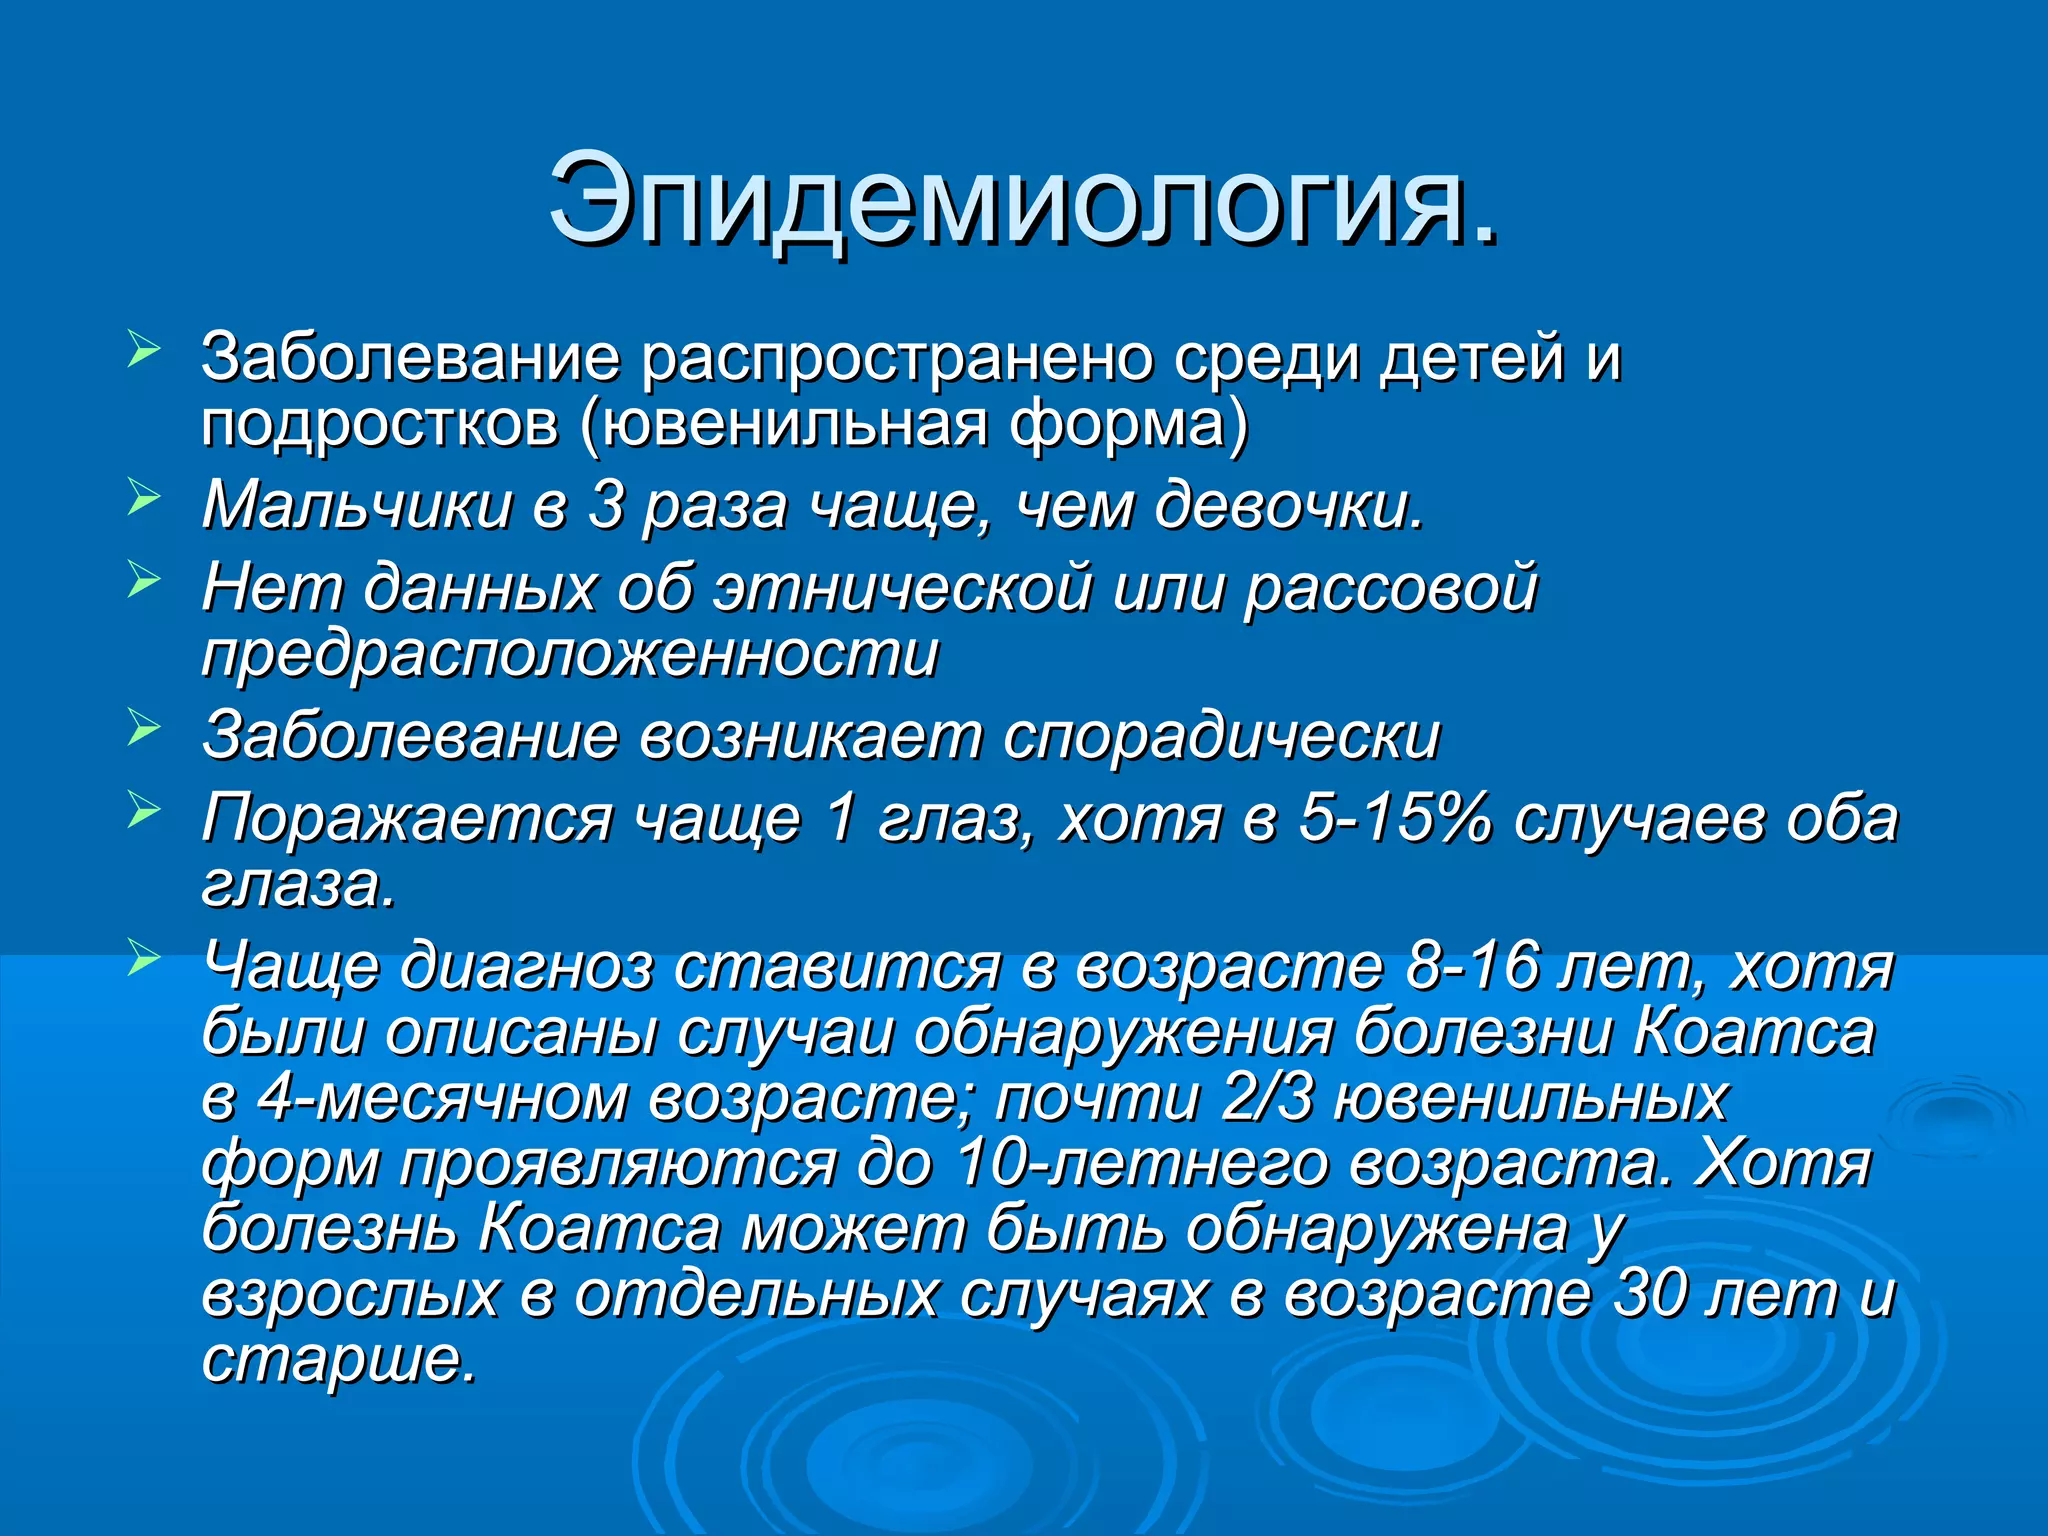

Болезнь Коатса - это идеопатическое заболевание, характеризующееся полиморфными изменениями сосудов сетчатки с массивной экссудацией, чаще всего у детей и подростков, с преобладанием среди мальчиков. Эпидемиология показывает, что заболевание проявляется, как правило, в возрасте 8-16 лет, но возможно его обнаружение и у взрослых. Основные проявления включают ретинальные аномалии, субретинальную экссудацию и постепенно прогрессирующую потерю зрения.